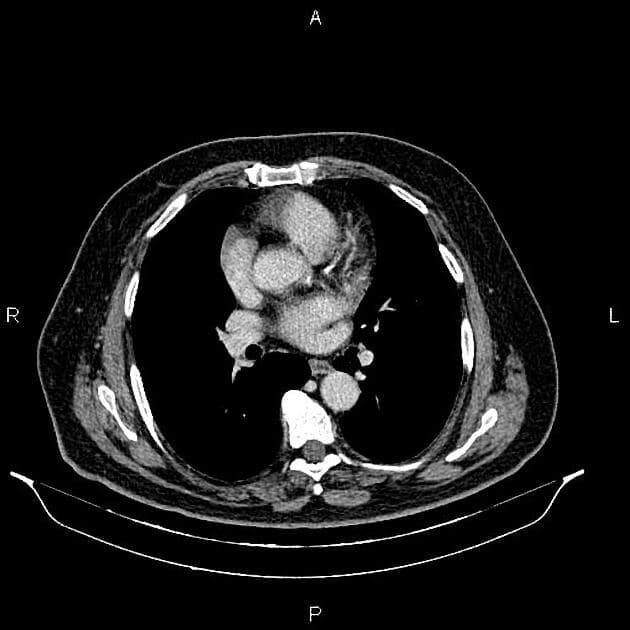

- Một khối nang khu trú một phần lồi ra ngoài (exophytic) kích thước 48 mm, thành dày ngấm thuốc (enhancement) và có các vách ngăn cùng các nốt ngấm thuốc lệch tâm (eccentric enhancing nodules) được ghi nhận ở phần giữa của thận phải.

- Một vài mạch máu tuần hoàn bàng hệ (collateral circulation) nhỏ giãn được ghi nhận trong khoảng gian thận (perinephric space).

- Ngoài ra, thấy một vài nang đơn thuần (simple cortical cysts) ở vỏ thận hai bên.

Khối nang thận - phân loại Bosniak IV (Renal cystic mass - Bosniak class IV)

- "Các đặc điểm hình ảnh chính bao gồm thành dày ngấm thuốc, vách ngăn ngấm thuốc và các nốt ngấm thuốc lệch tâm."